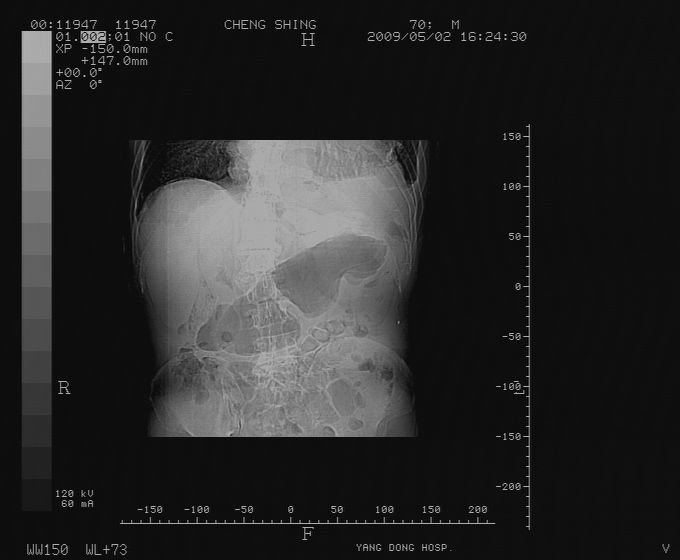

标题: CT19743:男70岁,肺部疾病入院,B超发现肝右叶占位,CT [打印本页]

标题: CT19743:男70岁,肺部疾病入院,B超发现肝右叶占位,CT

肝表面塌陷,病灶周围有子灶,前面较大子灶强化符合肝癌表现,考虑肝癌肝转移可能性大.